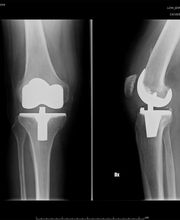

Il Dr. Grillo Pier Paolo, laureato con lode in Medicina e Chirurgia, è specializzato in Ortopedia, Traumatologia e Fisioterapia. Dal 1980 lavora presso il CTO di Torino, ove attualmente presta servizio presso la Clinica Ortopedica Traumatologica Universitaria in qualità di Dirigente Ortopedico - Traumatologo di I° Livello, che svolge la sua attività di sala operatoria, ambulatori specialistici e pronto soccorso. Si occupa prevalentemente di chirurgia del ginocchio e dell'anca con riferimento: Chirurgia protesica(totale, parziale, revisioni e reimpianti, trattamento delle complicanze settiche), Chirurgia artroscopica (ricostruzioni legamentose LCA-LCP, meniscectomie selettive, suture meniscali, trattamento dei danni cartilaginei),chirurgia della patologia rotulea (riallineamenti prossimale e distale,trattamento della lussazione recidivante,condroplastica, ricostruzione legamento patello-femorale) chirurgia delle deformità (ginocchio varo o valgo), traumatologia, patologie degenerative post-traumatiche. Ha partecipato a numerosi congressi, convegni e corsi di aggiornamento in Italia e all'estero; ha partecipato a numerosi Cadaver Lab all'estero in qualità di Tutor; è coautore di numerose pubblicazioni scientifiche edite a stampa. Per contatti e prenotazioni: studio medico: Studio Medico Crocetta - c.so Galileo Ferraris 107, Torino tel.: 011-5818892. Per ulteriori informazioni visitate il sito: www.studiocrocetta.it.